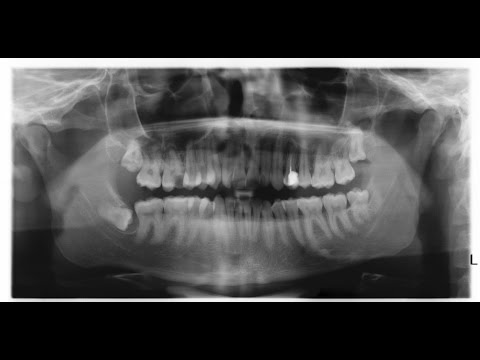

Hiányzó fogak pótlása, műgyökér beültetéssel